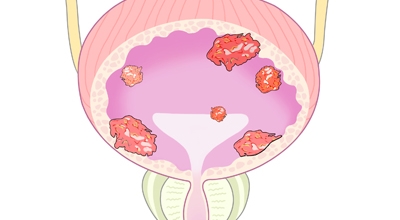

방광암 치료법

방광암 치료법은 경요도 절제술을 하게 되는데요. 이 후 종양의 개수나 크기, 재발 기간 등에 그렇기 때문에 항암제를 주입하는 등 여러가지 치료를 하게 되는데요. 상황에 그렇기 때문에는 방광 적출술이 필요할 수 있고, 재발이 잦기 때문에 방광암 치료법을 시행하면서도 주기적인 추적 검사를 해야 합니다.

방광암 생존율

방광암 생존율은 다른 암에 비해 완치율이 높은 편이예요. 초기에 발견해서 치료를 한다면 방광암 생존율은 약 77% 이상이라고 합니다. 이미 전이가 된 경우, 당연히 방광암 생존률이 낮아질 수 밖에 없어요. 다만 방광암 1기, 2기여도 치료 후 재발이 잘 되는 암이라서 치료와 함께 원인을 제거하고 생활습관을 고치는 것이 필요합니다.